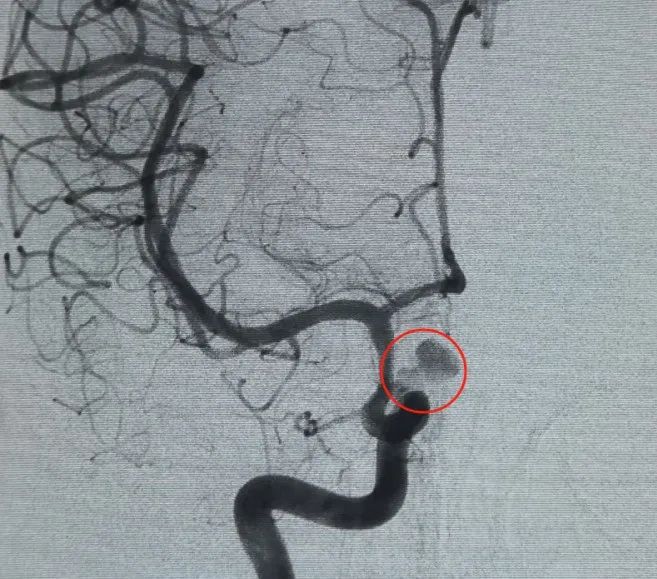

Um Perfiller®3mm × 6 cm bobina expansível e um Perfiller®3mm × 2 cm bobina expansível foram então colocados para completar a oclusão do pescoço. Posteriormente, uma Nuva®Desviador de fluxo (TJED-D-5.0-16) foi entregue e implantado no pescoço do aneurisma. A angiografia de seguimento tanto na visão anteroposterior quanto na lateral confirmou excelente cobertura, boa aposição da parede e clara radiopacidade, com acentuada estagnação do contraste.

O procedimento foi realizado sem complicações, e o paciente recuperou-se sem déficits neurológicos.